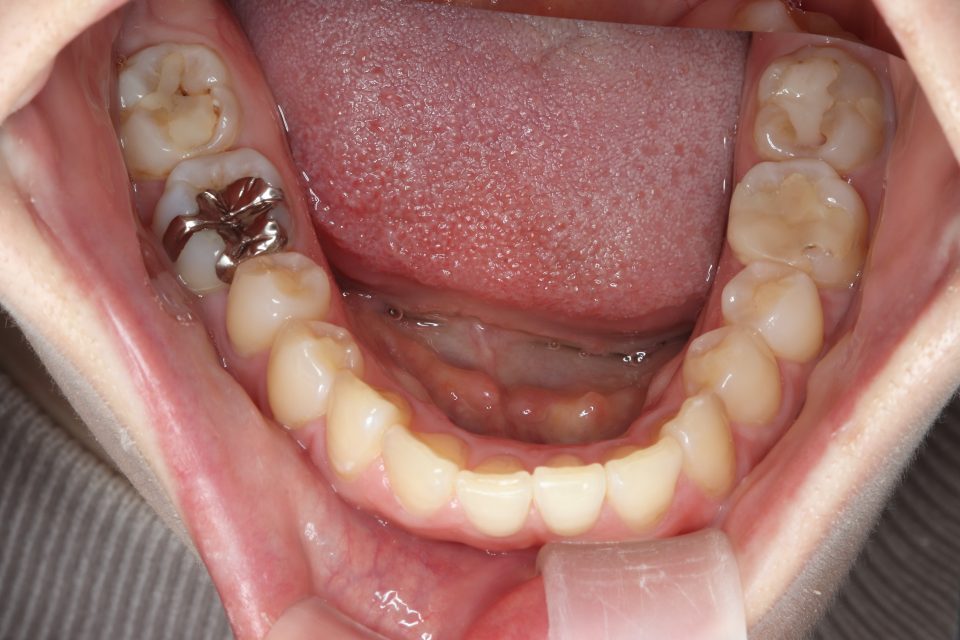

矯正治療前

部分的な矯正治療を希望され、

マウスピース型の矯正治療装置を使用し、歯のやすり掛け(IPR)を行いました。